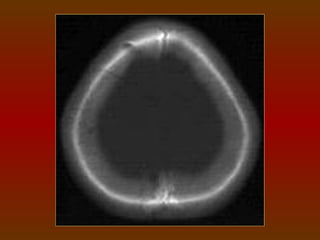

TC CRÂNIO AXIAL

COM JANELA ÓSSEA

TC CRÂNIO AXIAL COMJANELA ÓSSEA